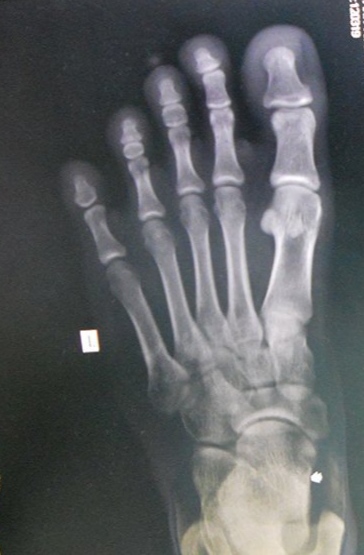

Mày xem đối chiếu với vị trí m đau coi

Dung ka Tao là gay 9/6/23 #21 Mày xem đối chiếu với vị trí m đau coi Đính kèm IMG_20230608_184217.jpg 67.9 KB · Xem: 14 IMG_20230608_184247.jpg 142.4 KB · Xem: 15

Fear of Gout Tao là gay Chủ thớt 9/6/23 #22 Dung ka đã viết: Mày xem đối chiếu với vị trí m đau coi Nhấn để mở rộng... đau ở đốt gần 1 ngón cái đó mày, lúc đi bộ còn nhói nhói dưới ngón cái nữa, giống quá mày ơi huhu

Dung ka đã viết: Mày xem đối chiếu với vị trí m đau coi Nhấn để mở rộng... đau ở đốt gần 1 ngón cái đó mày, lúc đi bộ còn nhói nhói dưới ngón cái nữa, giống quá mày ơi huhu